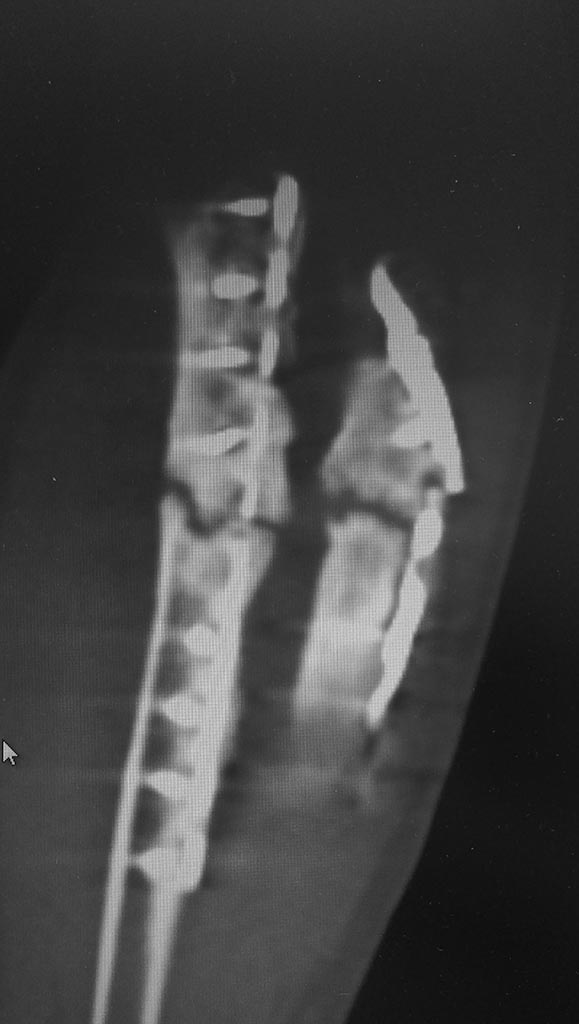

[Ortho] Ложный сустав обеих костей предплечья, несостоятельность остеосинтеза

Вложение не в текстовом формате было извлечено…

Имя     : P_20200312_133517_1.jpg